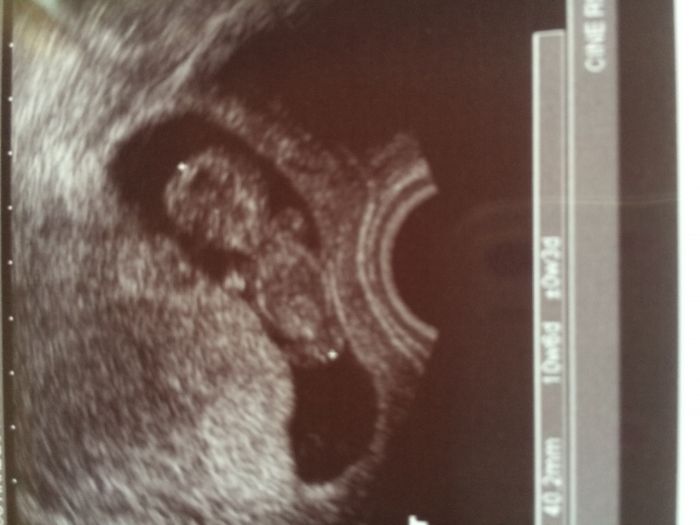

[1014507] No, tak za prvé pro mě velké překvápko, že mi brali jen jednu zkumavku krve, takže za 10 vteřin po všem:-)...ultrazvuk super, srdíčko krásně bije a posunuli jsme se velikostně o 2 dny dopředu, takže dnes už 10+6tt a pak doktor říkal, že mimi je krásný a velký...jinak 24.8. jdu na druhou část screeningu, tedy už jen na utz a rovnou budeme mít výsledky:-)

Řekl mi to a mám to i na fotce, kterou jsem zadáčo dostala:-)...za 14 dní vyrostl o více než 2 cm, teď má 4,2cm!!!